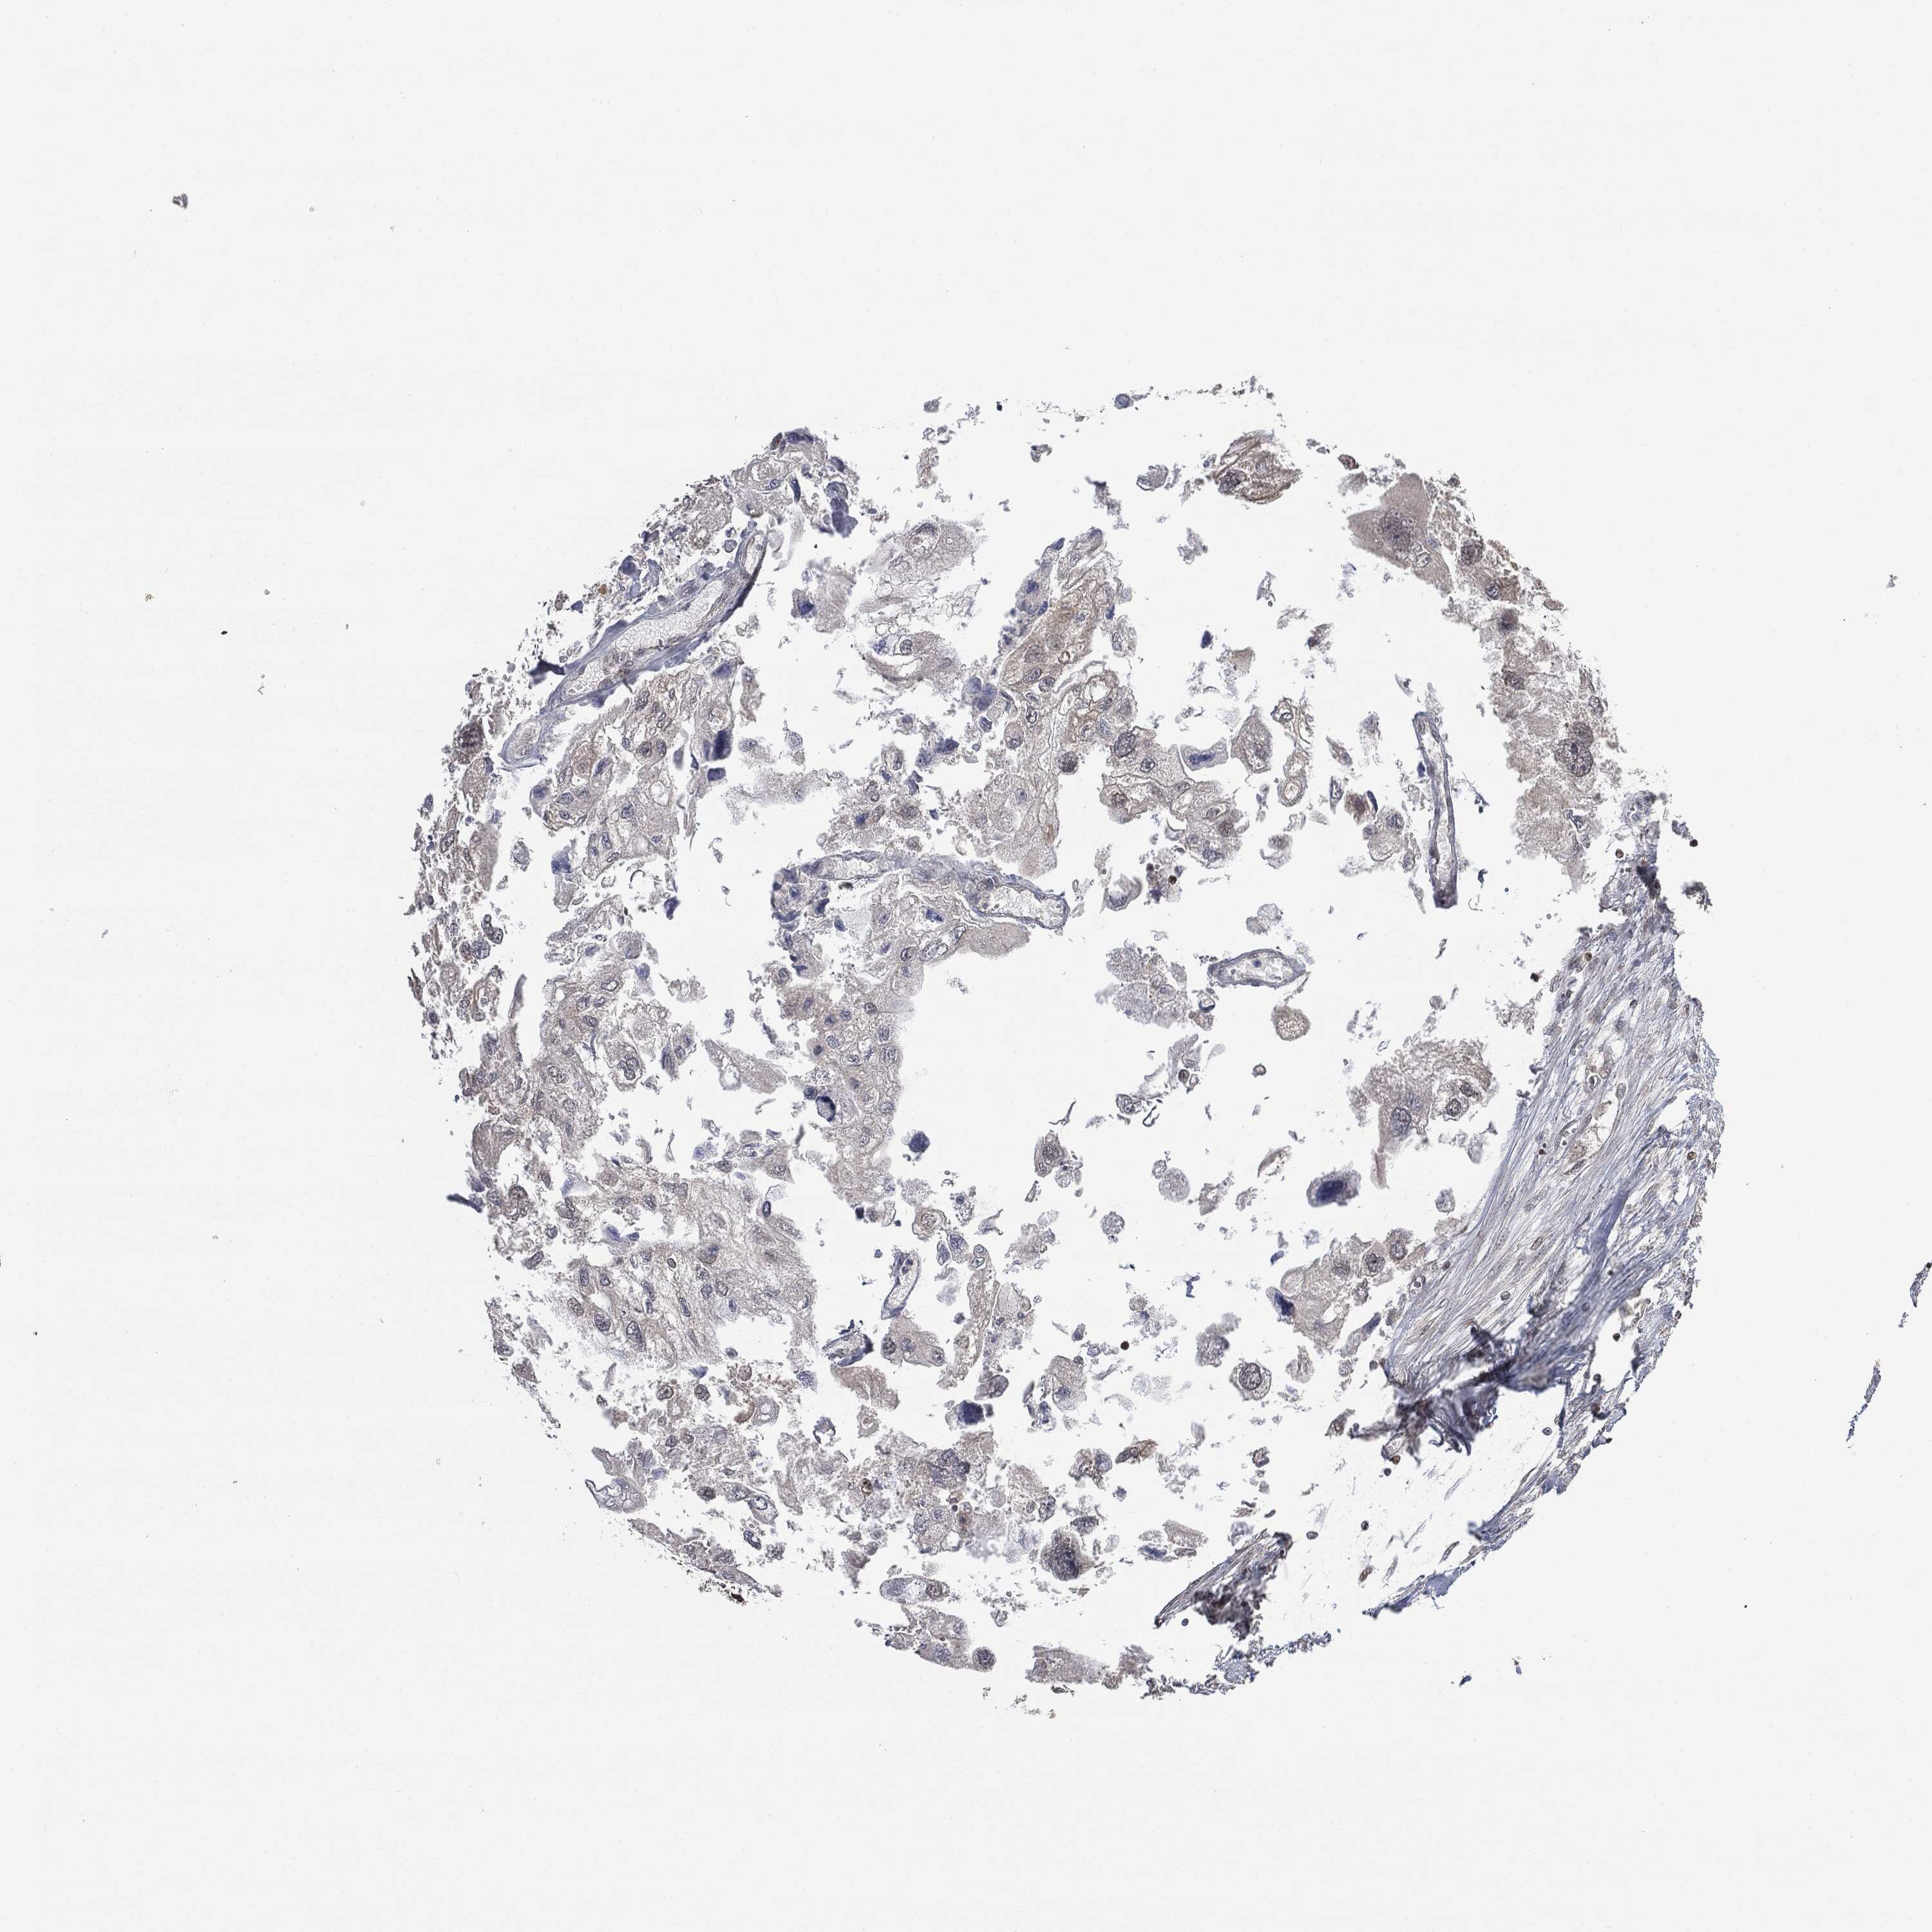

UROTHELIAL CANCER - Protein expressioni

A mouse-over function shows sample information and annotation data. Click on an image to view it in a full screen mode. Samples can be filtered based on level of antibody staining by selecting one or several of the following categories: high, medium, low and not detected. The assay and annotation is described here.

Note that samples used for immunohistochemistry by the Human Protein Atlas do not correspond to samples in the TCGA dataset.

Antibody stainingi

Antibody staining in the annotated cell types in the current human tissue is reported as not detected, low, medium, or high, based on conventional immunohistochemistry profiling in selected tissues. This score is based on the combination of the staining intensity and fraction of stained cells.

Each image is clickable and will lead to virtual microscopy that enables deeper exploration of all samples and also displays staining intensity scores, fraction scores and subcellular localization as well as patient and tissue information for each sample.

CAB080478

Urothelial carcinoma, High grade

Urothelial carcinoma, Low grade

Adenocarcinoma, NOS